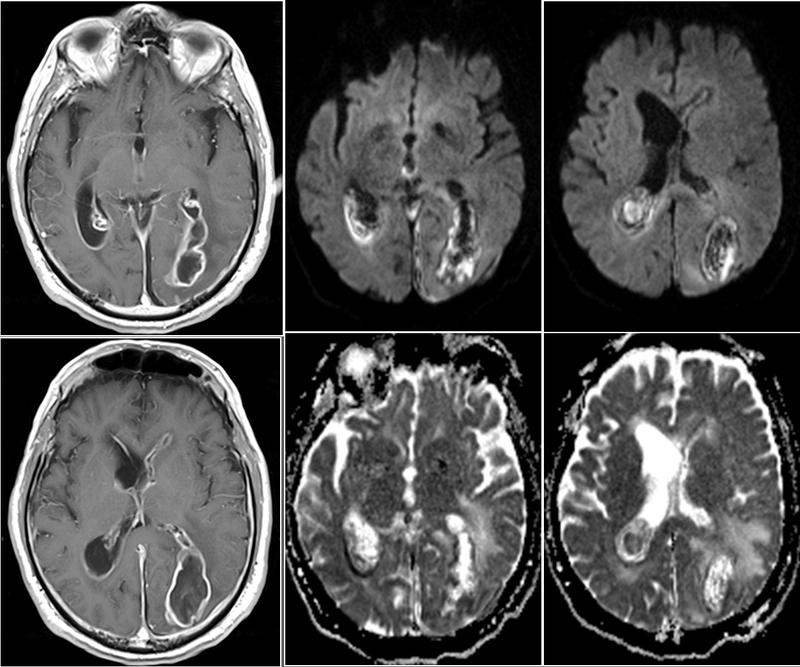

Việc chẩn đoán viêm não do sán chó gây ra cũng không đơn giản. Phải dựa vào rất nhiều yếu tố như vừa nêu hoặc phải chụp CT hoặc MRI não bộ để chẩn đoán bằng hình ảnh.

Dùng phương pháp chụp CT hay MRI sọ não nhằm mục đích tìm hình ảnh tổn thương trên não. Tìm hình ảnh gợi ý tổn thương viêm màng não đồng thời có thể có hình ảnh tổn thương não tủy đi kèm. Trường hợp quá khó chẩn đoán và nặng có thể sẽ sinh thiết não.